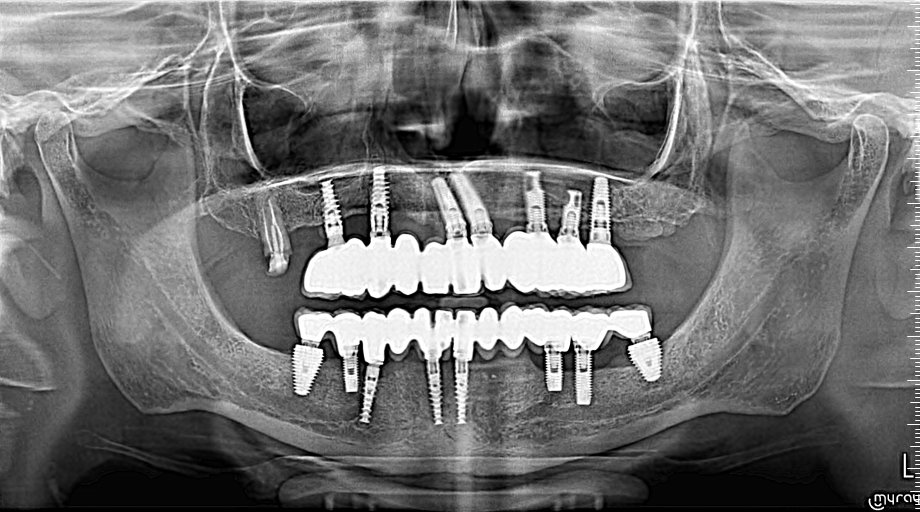

Llega este paciete a la consulta para recambio de ambas Hibridas. Lo ùnico que pude conseguir con su antiguo dentista fue informacion de los IOI de posicion 3.6 y 4.6 [...]